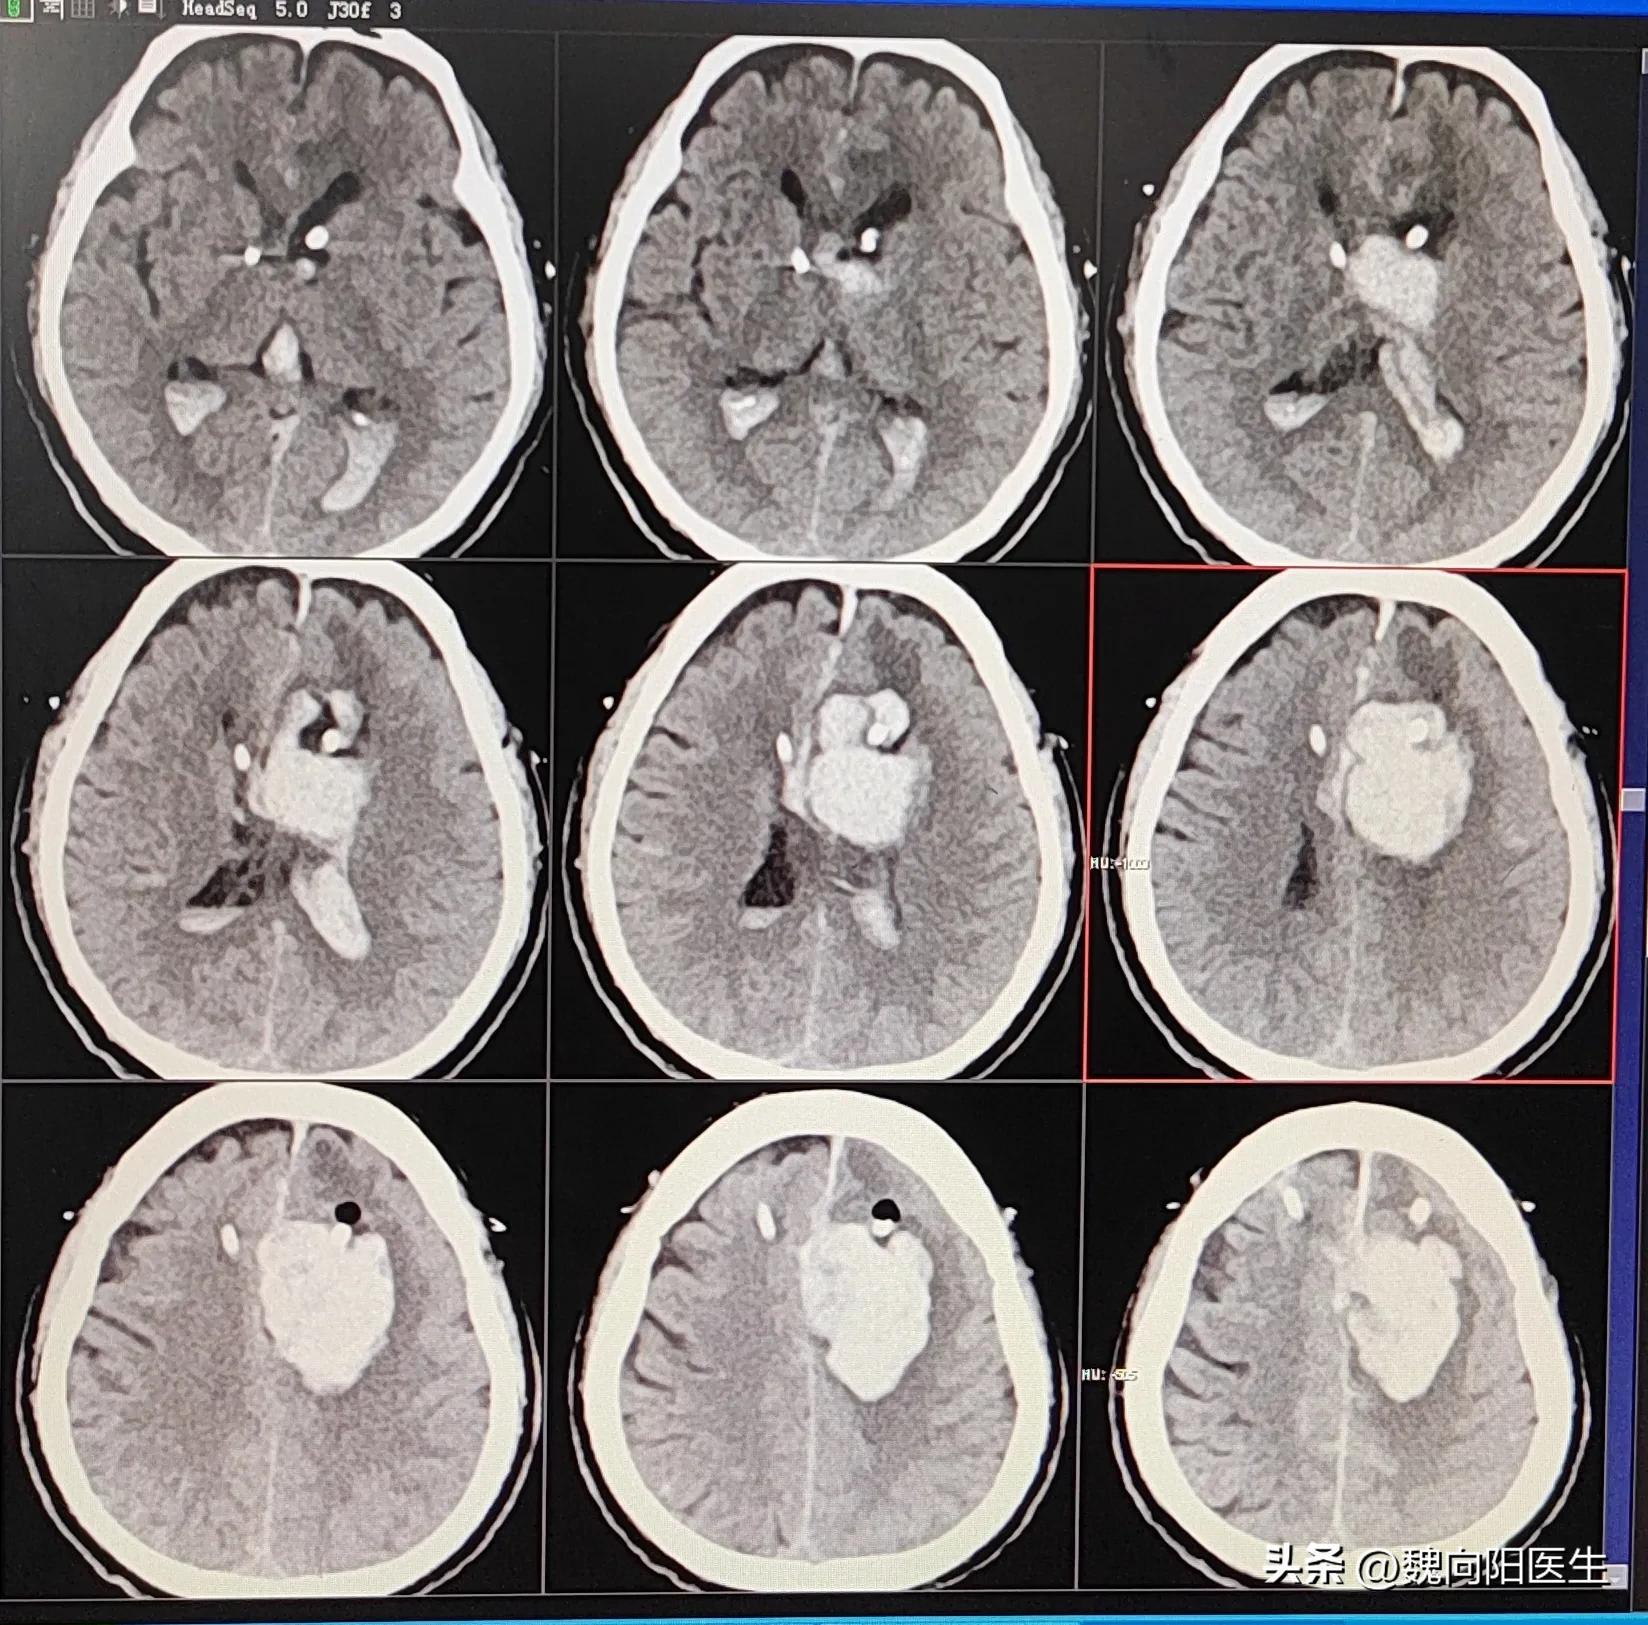

今天收治了一例男性患者,因为心房颤动,长期服用华法林。这次住院是因为脑出血而收住院的。

患者家属反复强调,患者只是存在心脏病,并没有颅脑疾病,为什么会发生脑出血?他们很不理解。